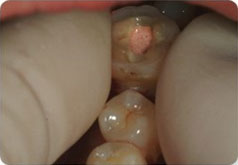

STEP 3

치료한 치아를 제자리에 넣습니다.

STEP 4

수술 후 7~8주후면 치아가 단단히 고정되며 보철치료 후 사용합니다.